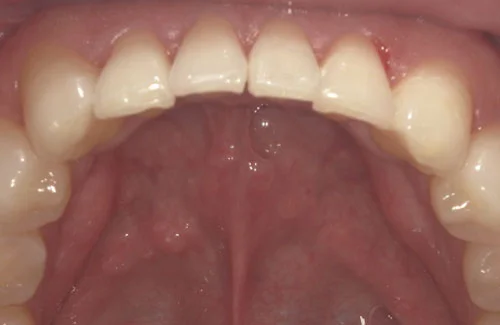

ウィ・スマイルの症例

- 症例1

治療期間 4カ月

治療費 23.1万円(月額1,925円~)

※上顎前歯部、下顎前歯部の叢生をマウスピース型矯正装置で改善したケース。矯正治療上のリスクとして、治療中の虫歯、歯根吸収、歯肉炎 ・歯周炎の発生などが考えられる。